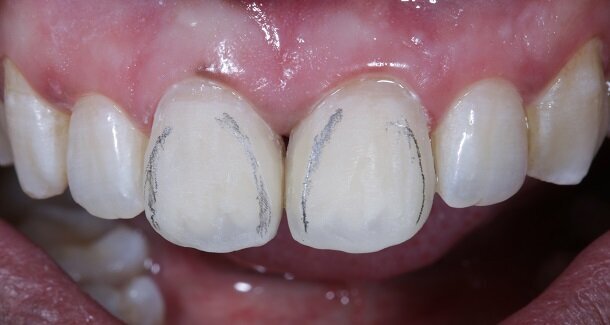

Presenting a case of a 22 yr old male, who reported to our dental office with fractured Maxillary Central incisors many years ago [Figures 1 and 2]. On examination both Maxillary Central incisors had fractures with pulp exposures. IOPAR showed large peri-apical lesions in both teeth. There was no mobility seen in either teeth, but discolouration was seen in both. Non-surgical Endodontic treatment followed by Bleaching and Direct composite restorations (2 weeks post bleaching) were planned.

The figures show the clinical work flow involved. In the 1st appointment Oral prophylaxis, oral hygiene instructions were followed by an impression that was sent to the lab for a wax up [Fig 3 and 4]. In the subsequent appointments, Endodontic treatment was followed by Intra and extra coronal office bleaching using the Pola office bleaching kit. After two weeks, the shade stabilised post bleaching. Shade selection, rubber dam isolation and preparation was done on both the teeth to receive Direct composite veneers so as to close the midline diastema as well as correct the fractured teeth and the slight mal-alignment. Controlled Body Thickness (CBT) technique of layering was used with 3M Z350XT shades - Dentin shades A3, A2 and Enamel shades A2, clear translucent [Figures 5 to 11]. This was followed by the Finishing and polishing protocol as described in the figures.